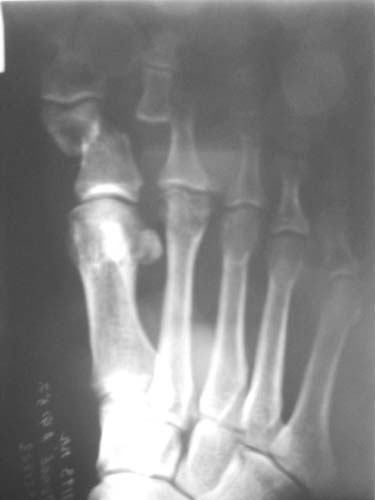

Diagnosis: smash of the front parts of both feet, multiple open fractures of metatarsus bones and phalanxes of toes, contused-scalped wounds.

Right: scalped wound on the sole (10*8cm), partial injury of toes flexion tendons, incomplete tearing off of I-III toes (on the back piece);

Left foot